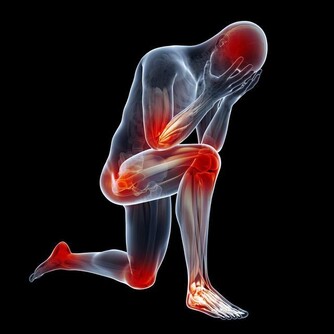

1、關節疼痛、紅腫

大量尿酸結晶沉積關節腔內,可誘發痛風性關節炎。患者往往在深夜突然出現關節疼痛,如刀割般疼痛,嚴重時會影響走路,伴關節紅腫,局部皮膚溫度升高的症狀。

首次發作以第一蹠趾關節(大腳趾與腳掌連接的關節)最常見,佔90%左右,踝關節、膝關節、腕關節、指間關節等也會受累。